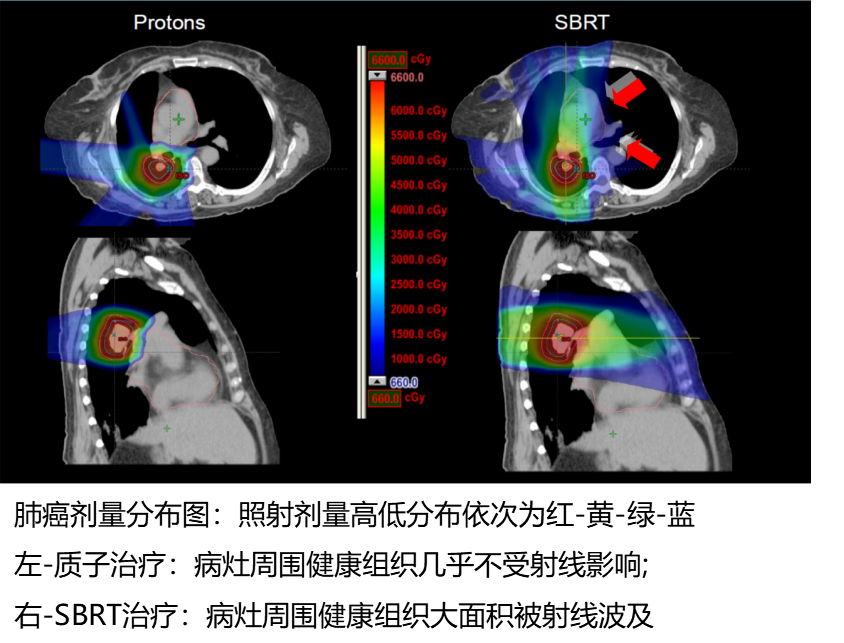

早期NSCLC首选手术,5年生存率为60%-80%。但很多患者因年龄,心肺功能差或其他合并症,或者主观意愿而不能手术。这时候,放疗成为最好的选择。立体定向放射治疗(SBRT)是较为常见的放疗方式,SBRT通常利用多个束或弧,使用较低剂量的射束面对较大体积的肺部病灶,治疗同时也导致肺毒性,这使得患有严重呼吸道疾病的患者苦不堪言。研究表明,当SBRT用于治疗中央或超大中心病变时,支气管,脉管系统和周围关键结构的毒性风险较高,必须使用小剂量照射避免毒性,这时候治疗效果又大打折扣。

与光子(传统放疗如伽马刀、托姆刀、SBRT)放疗不同,质子放疗的物理特性允许能量在特定深度沉积,照射曲线形成布拉格峰。即到达肿瘤部位释放最大剂量,通过肿瘤后实现能量快速衰减,允许超出肿瘤深度的正常组织接受很少或没有剂量的照射,到达肿瘤前剂量也很少释放。该性质使质子治疗具有更好的剂量分布,有效消灭肿瘤的同时限制剂量到肿瘤附近的关键组织结构,保护其不受损伤。

在肺癌中,质子治疗可以最小化对肺和周围结构的剂量,最大限度地降低治疗毒性,也允许接近关键结构肿瘤的照射剂量递增,实现更好地控制肿瘤。减少对附近健康组织的剂量也可以更安全地使用多模式治疗,可以在局部复发的情况下再次照射。早期NSCLC中质子治疗优于光子治疗的益处已经在很多研究中得到证实,可改善射线对肿瘤覆盖率,减少肺、心脏、食管和脊髓的损伤。